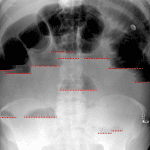

Age: 46

Sex: Male

Indication: Diffuse abdominal pain

Findings

- Multiple dilated loops of small bowel throughout the abdomen measuring up to 5 cm in diameter with multiple air-fluid levels on upright imaging

- Paucity of colonic and rectal gas

- No evidence of pneumoperitoneum on upright images

- Enlarged cardiopericardial silhouette

Diagnosis

- Small bowel obstruction

Findings are concerning for high-grade distal small bowel obstruction. No evidence of pneumoperitoneum. Consider CT for further evaluation.